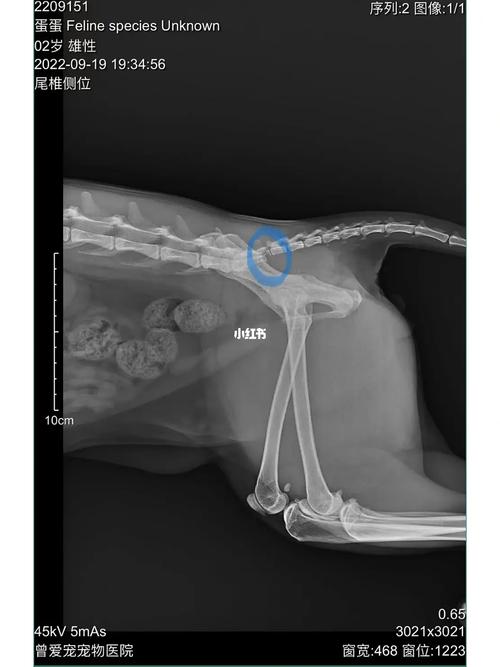

如果发现猫咪尾巴有一段像骨折一样,很可能是因为尾巴骨头出现了断裂。 建议主人及时带猫咪去医院进行X光检查,以确诊尾巴的状况。 正常情况下,猫咪的尾巴由多块骨头组成,虽然灵活但不会弯曲。 如果尾巴出现弯曲,可能是由于尾巴部位的骨头断裂所致。 幼猫可能不会表现出强烈的疼痛感,尤其是在出生后不久。

猫咪尾巴有一段像骨折一样很可能是骨头出现断裂引起的,建议主人及时带猫咪去医院拍片检查。正常的猫咪尾巴是由很多块骨头组成的,虽然很柔软但不会有折,如果发现有折说明猫咪尾巴在弯折处的骨头很可能出现了断裂,这种情况需要拍摄X光做最后的确诊。

如果发现猫咪尾巴有一段类似骨折的状况,很可能是因为尾巴的骨头出现了断裂。 应该及时带猫咪去宠物医院进行X光检查,以确诊尾巴的状况。 猫咪的尾巴由多块骨头构成,虽然灵活但不易折断。若出现折断现象,可能是骨头断裂所致。